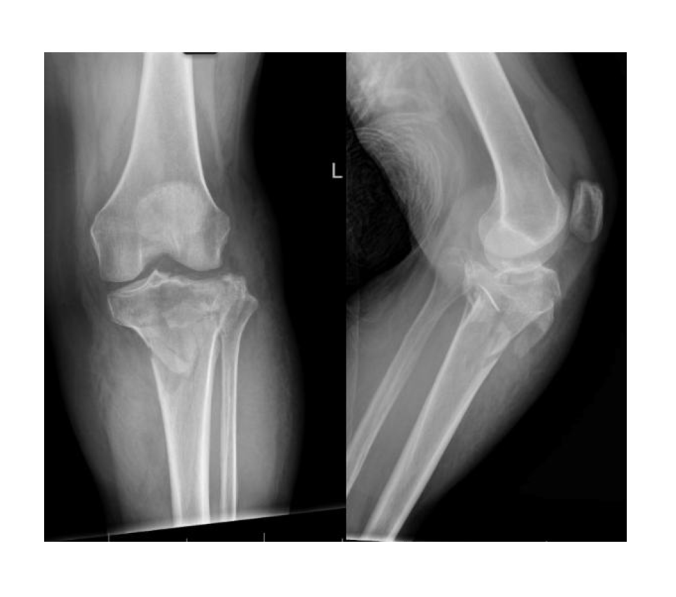

A 57‑year‑old woman with type II diabetes presented after a fall with a swollen, fractured leg. Initial management planned closed reduction and external fixation, but surgical prioritization was challenging due to competing trauma cases.

Non‑invasive soft‑tissue compressibility measurements using Compremium Quantis ST were performed on the injured leg to support decision‑making, calculating CP value as the percent change in compartment thickness between low and high applied pressures.

Severe hyperglycemia and markedly reduced anterior compartment compressibility (average 5%) indicated evolving compartment syndrome.

Surgery was prioritized, and the patient was taken immediately to the OR for fasciotomy and external fixation. All muscle was viable intraoperatively, and wounds were closed on postoperative day 4–5. Objective measurements enabled timely intervention, preventing irreversible muscle damage, particularly in a high‑risk diabetic patient.